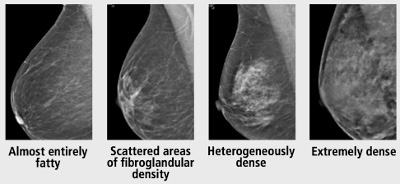

- According to the 5th edition of the ACR BI-RADS® Atlas, visual estimation of breast fibroglandular composition should be defined by one of the following four descriptions:

- Almost entirely fatty

- Scattered areas of fibroglandular density

- Heterogeneously dense

- Extremely dense

👉The U.S. population distribution of breast density is as follows:

- 10% almost entirely fatty

- 40% scattered areas of fibroglandular density

- 40% heterogeneously dense

- 10% extremely dense

👉Women with heterogeneously dense or extremely dense breasts are considered to have “dense breasts.”